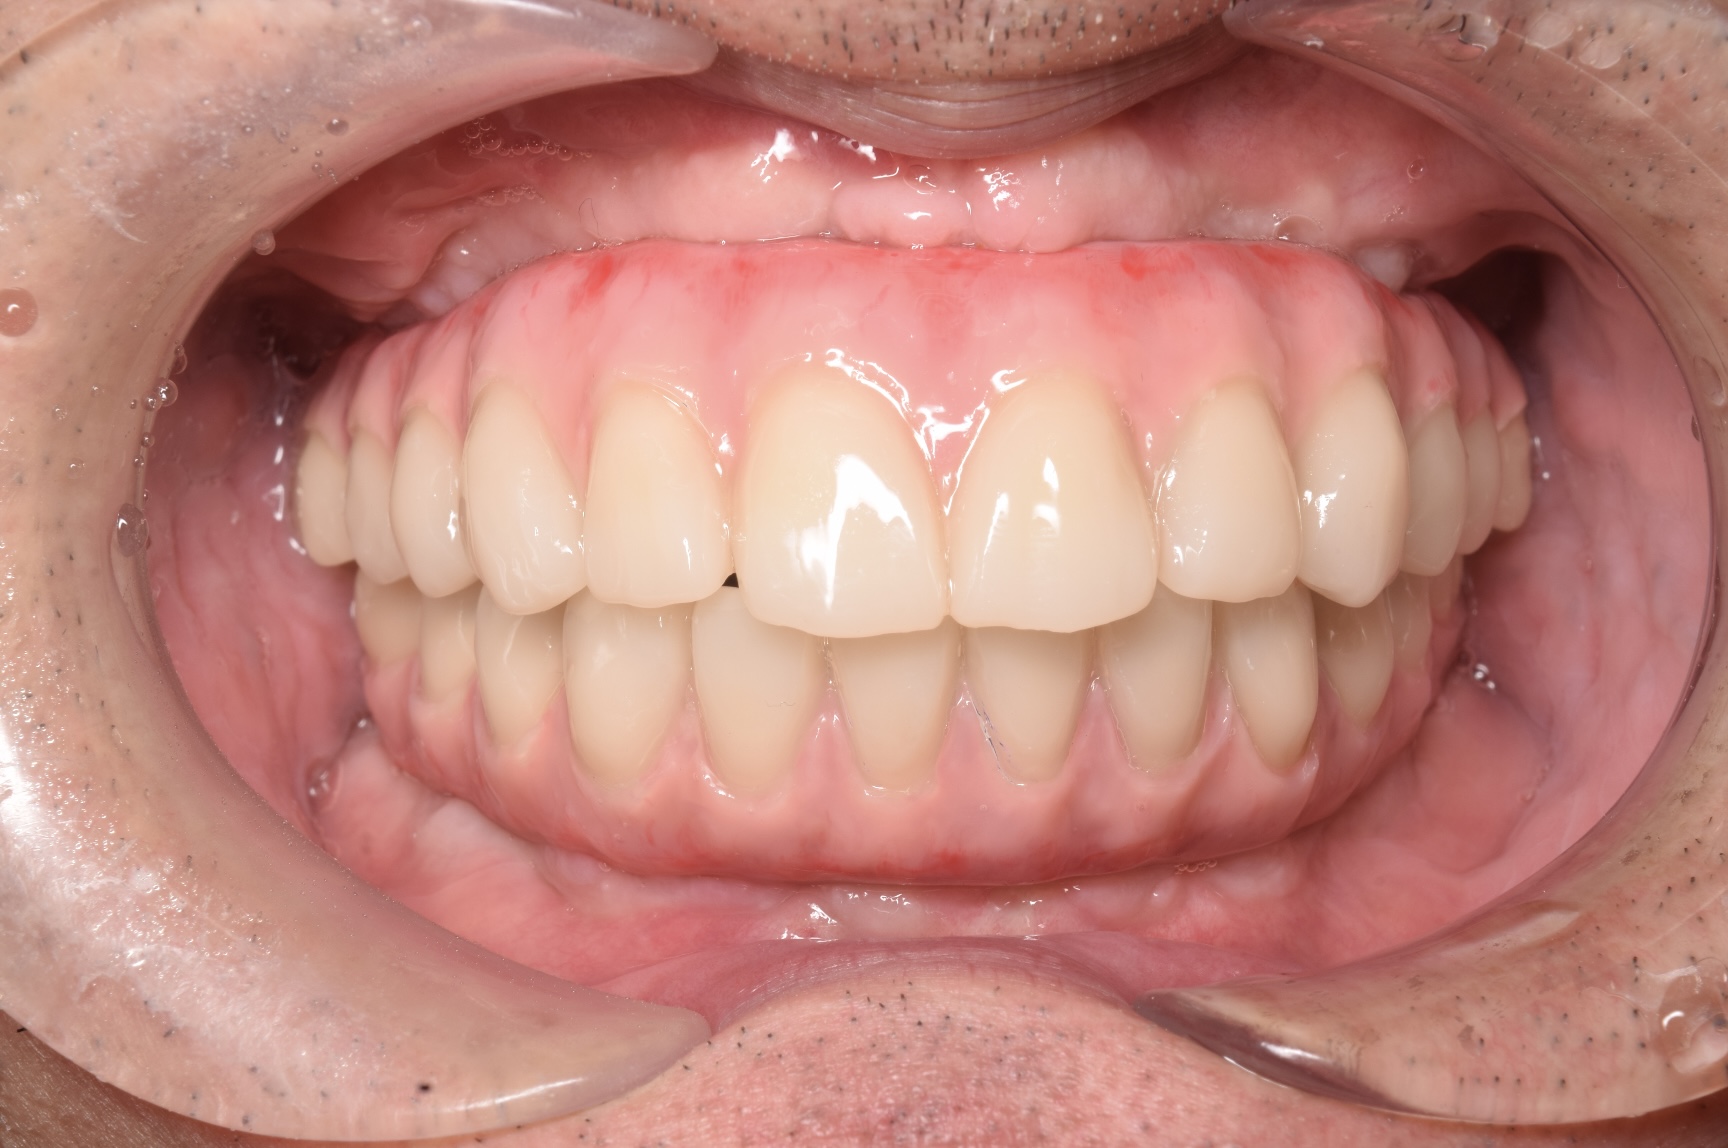

CASE

1